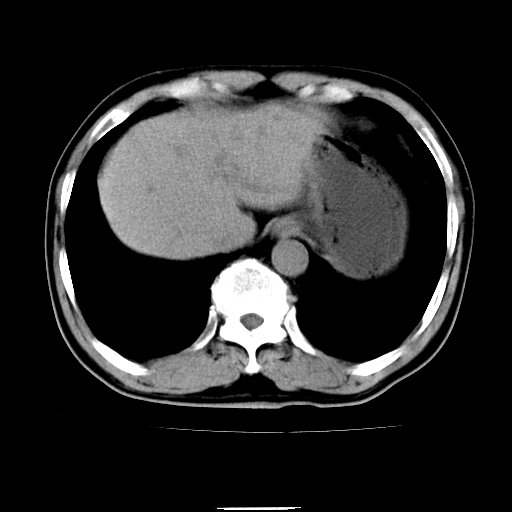

以下是引用chenqiong在2010-3-25 20:56:00的发言:[br]1、胆囊炎,胆囊息肉[br]2、肝内胆管及胆总管扩张,胆总管下端结石[br]3、十二指肠乳头旁憩室

以下是引用zxl51642在2010-3-26 10:47:00的发言:[br]胆囊炎,胆囊息肉,胆总管扩张,但未看到明显肿块,肝内胆管扩张不像恶性,炎性狭窄或阴性结石可能吧,建议mrcp,右肾小囊肿